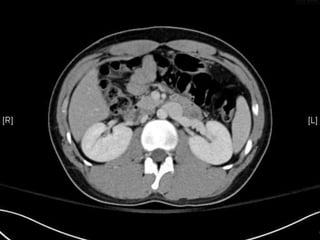

• CT:

 Shanmuganathan(2004)

 Sen:97%, spe:98%, accuracy:98% in penetrating stab wds

 Velmahos(2005)

 GSW: Sen 90.5, Spe: 96%

Radiology 2004:231:775-784

J trauma 2005:59:1155-1161